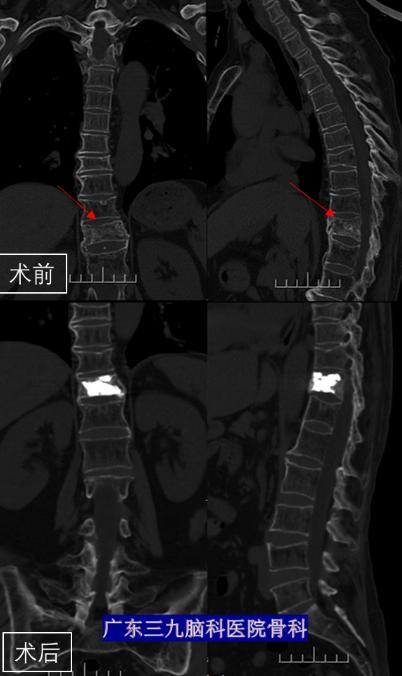

征得患者及家属同意后,骨科团队在局麻下为王姐实施“经皮穿刺胸11椎体成形术”。手术仅在患者的背部开了一约2mm切口,然后用穿刺针在C臂机透视下经皮肤穿刺进入椎体,建立工作通道将骨水泥注入椎体稳定塌陷的椎体。术中,柴亚胜多次透视确认患者胸11椎体内骨水泥充盈饱满,无渗漏。手术成功。

术后,王姐胸腰背部疼痛明显缓解,第二天就能正常下地活动。